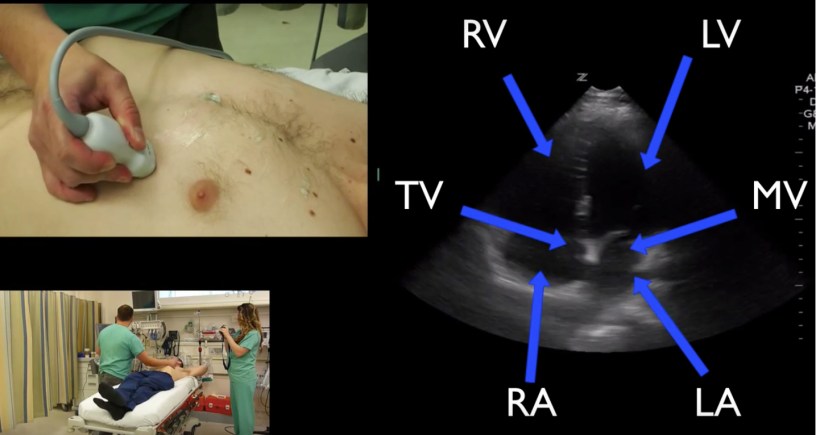

Sono Medical School, Sono Photo, Sono Stuff #POCUS #Cardiac #Anatomy in the apical 4 chamber view with probe placement. #FOAMUS #FOAMED Date: July 27, 2016Author: Mike 0 Comments Share this: Share on X (Opens in new window) X Share on Facebook (Opens in new window) Facebook Like Loading...